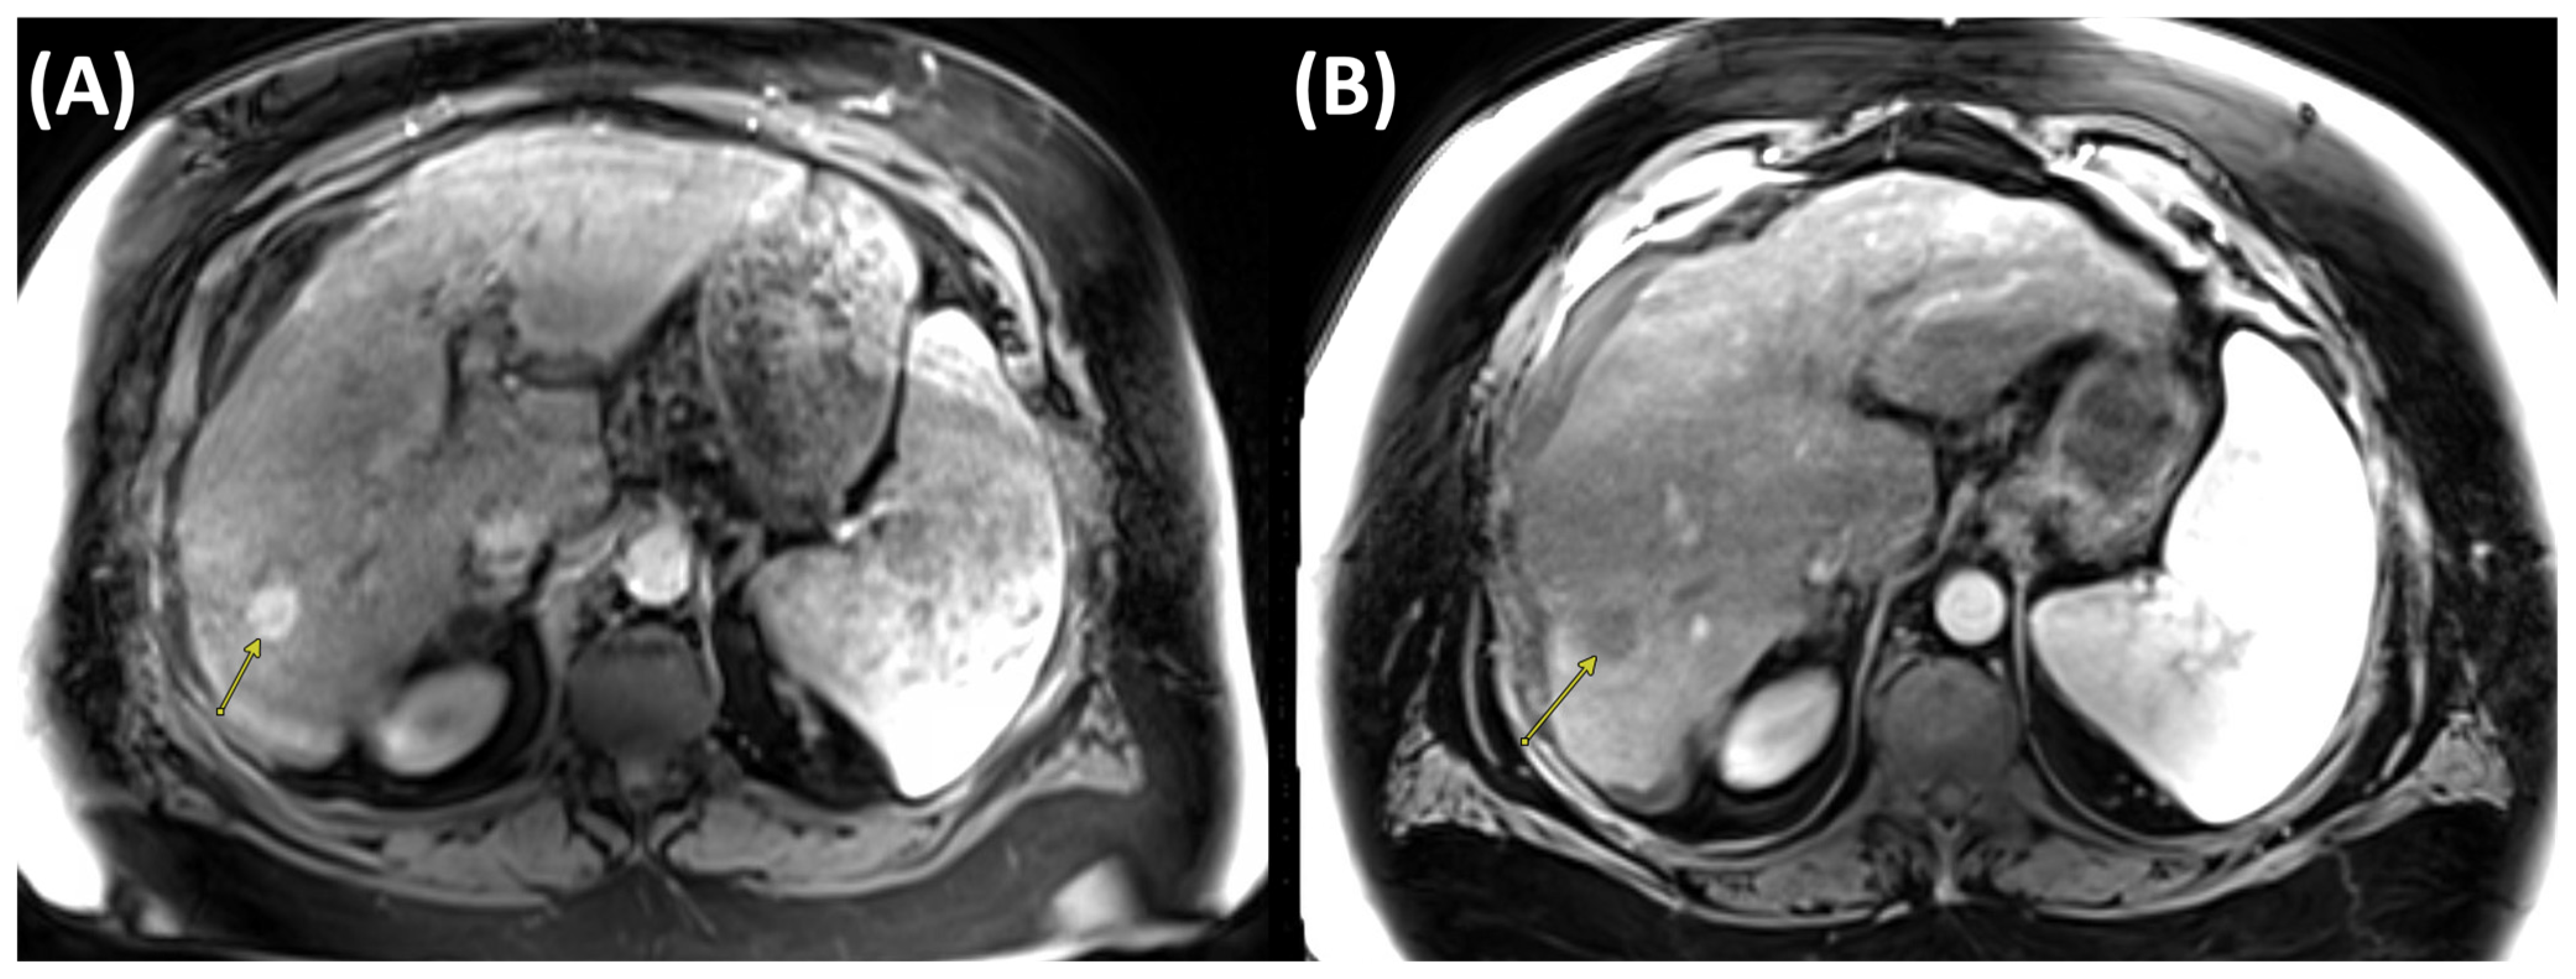

2.3. Cryoablation